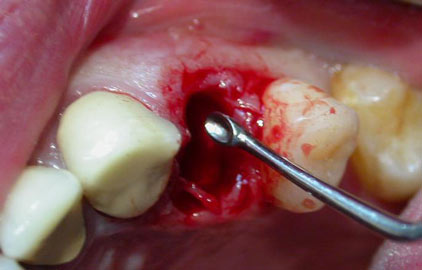

- Anestesia di superficie di Mepivacaina con adrenalina forte 1:100 000, previa iodizzazione di tutta l'emiarcata da trattare si è proceduto all’avulsione dei residui radicolari con tecnica chirurgica microinvasiva flappless (senza lembo a cielo chiuso ), cercando di salvaguardare la corticale ossea vestibolare e le pareti mesio-distali;

![]() |

Successivamente si è provveduto al raschiamento alveolare con cucchiaio

di Hemingway n° 2 e pulizia dello stesso alveolo da eventuali frustoli ossei,

con relativa radiografia endorale rvg di controllo del sito post estrattivo;